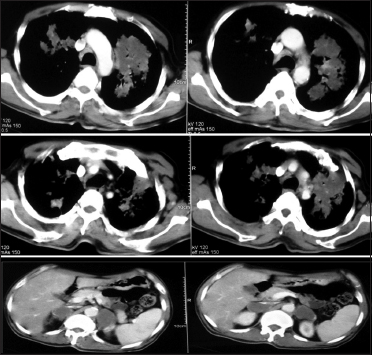

A 65-year-old male, smoker presented with complaints of dry cough, chest pain, and low-grade fever for the last 3 months in the pulmonary department. Multifocal dense consolidations involving bilateral lungs fields were discovered on simple chest X-rays [Figure 1]. His vital signs on admission were normal and laboratory results were white blood cells 5400/mm3, hemoglobin 15.2 g/dL, hematocrit 39.2%, platelet 188 k/mm3, and erythrocyte sedimentation rate 5 mm/h. A serology test and culture for mycoplasma and tuberculosis were all negative. Chest and abdomen computed tomography showed multifocal dense consolidations involving bilateral lungs with perihilar predominance and hypodense bilateral adrenal masses [Figure 2]. Bronchoscopic findings were nonspecific.

| Figure 2 Chest and abdomen computed tomography